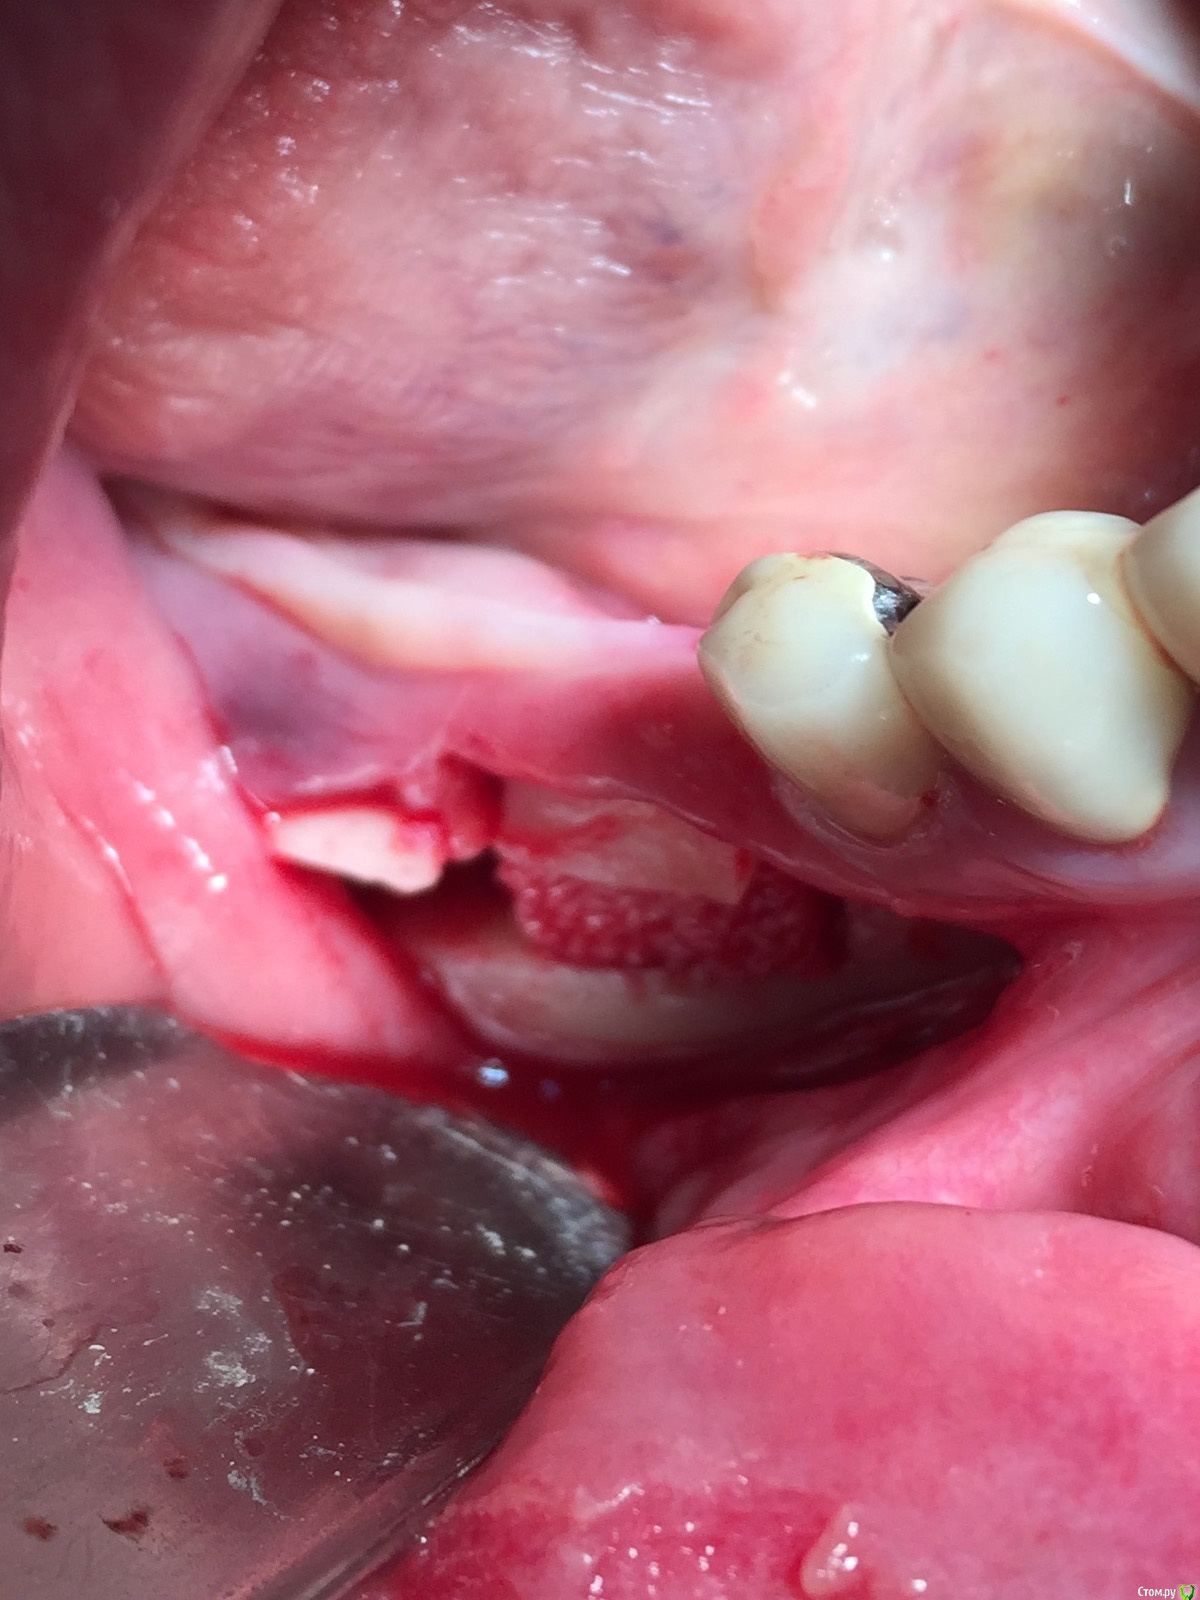

Популярный пост Глеб Митрофанов Опубликовано 22 октября, 2015 Популярный пост Поделиться Опубликовано 22 октября, 2015 (изменено) Горизонтальное расщепление Изменено 22 октября, 2015 пользователем Глеб Митрофанов 26 Ссылка на комментарий

Глеб Митрофанов Опубликовано 22 октября, 2015 Автор Поделиться Опубликовано 22 октября, 2015 круто! а срезы кт есть в этой области? и откуда треугольный ламинат брали, который в щели?Срезы есть , в телефоне найду , прикреплю . Ламинатик получился , путём истончение треснувшей крыши в дистальном отделе , думаю чего добру пропадать , заклинил его и винтом на всякий случай . Ссылка на комментарий

Глеб Митрофанов Опубликовано 22 октября, 2015 Автор Поделиться Опубликовано 22 октября, 2015 Ну вертикально же пропилы есть, да и подняли вертикально) ваш первый подобный кейс? Как ощущения?)))))) , вертикальные пропилы есть , но остеотомия горизонтальная . Кейс первый , ощущения от того , что сделал это конечно переполняют эмоциями , впереди вторая сторона . Учту опыт первой Ссылка на комментарий

Глеб Митрофанов Опубликовано 23 октября, 2015 Автор Поделиться Опубликовано 23 октября, 2015 Глеб,это вертикальное расщепление. Отлично получилось.Откуда микросом столько нашкрябали?В моём понимании вертикальное расщепление -это классическое расщепление с вертикальным продольным распилом . А стружка с дистальной крыши , который после причесывания микросом превратился в ламинат и с ветви , дистальнее распилов Ссылка на комментарий

Evikrol Опубликовано 23 октября, 2015 Поделиться Опубликовано 23 октября, 2015 Чем распилы проводили? И что за блок? Ссылка на комментарий

diesel87 Опубликовано 23 октября, 2015 Поделиться Опубликовано 23 октября, 2015 Чем распилы проводили? И что за блок?Китайский пьезо, блок от Остеобиола) Ссылка на комментарий

carloss Опубликовано 23 октября, 2015 Поделиться Опубликовано 23 октября, 2015 А гребень не очень язычно сдвинулся, особенно медиальная, довольно высокая стенка, которая судя по всему сейчас стоит перепендикулярно гребню?..языку не мешает?.. Спротезировать получится? И почему не горизонтальный нкр.. Хотя бы сосидж.. И вертикалить бы не надо было? 1 Ссылка на комментарий

Глеб Митрофанов Опубликовано 23 октября, 2015 Автор Поделиться Опубликовано 23 октября, 2015 А гребень не очень язычно сдвинулся, особенно медиальная, довольно высокая стенка, которая судя по всему сейчас стоит перепендикулярно гребню?..языку не мешает?.. Спротезировать получится?И почему не горизонтальный нкр.. Хотя бы сосидж.. И вертикалить бы не надо было?Гребень не сдвинулся , да и языку вроде ничего не мешало , отек спадёт - посмотрю конечно ещё раз . А вертикаль надо было , высота клинических коронок в два выше была бы Ссылка на комментарий